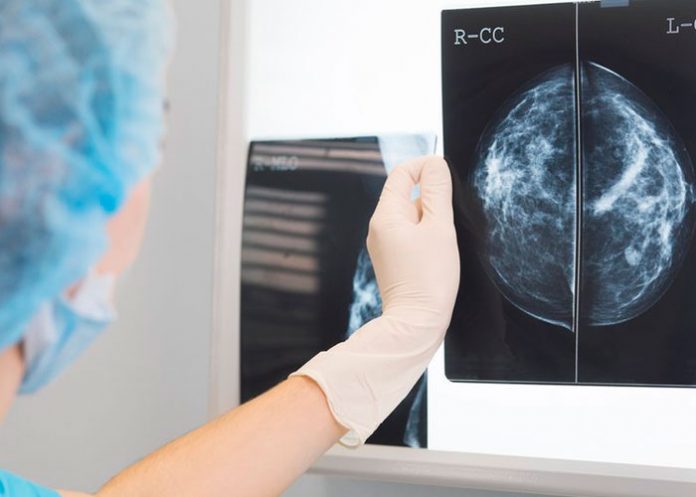

El nuevo método para detectar el cáncer de mama que puede ayudar a los médicos implica el uso de inteligencia artificial al examinar las mamografías y es capaz de determinar si el paciente está enfermo. Probado por científicos alemanes quienes compartieron el resultado en ‘The Lancet Digital Health’.

La investigación compara directamente el uso de una inteligencia artificial para la detección de este tipo de cáncer y determinó que la fórmula más efectiva para detectar correctamente los tumores es combinando las tareas del radiólogo con la tecnología.

En su experimento, los científicos demostraron que, ambos por separado, tienen peores resultados que si trabajan en equipo.

De hecho, analizando juntos, inteligencia artificial y radiólogo, las radiografías, los resultados a la hora de detectar el cáncer de mama son un 3,6 % mejores que un médico trabajando solo. Además, el trabajo en equipo provocó menos falsas alarmas.

Además de esta ventaja, trabajar con dichos sistemas de inteligencia artificial podría ayudar a salvar vidas al detectar cánceres que los médicos pasan por alto; así como liberar la carga de trabajo de radiólogos que, según ‘Technology Review’, no se dan cuenta de uno de cada ocho cánceres que ven en las radiografías.

Inteligencia artificial que es capaz de detectar más rápido el cáncer de mama

El software de inteligencia artificial que se está probando en Alemania ha sido desarrollado por Vara, una startup con sede en Alemania. Esta herramienta ya se utiliza en más de una cuarta parte de los centros de detección de este tipo de cáncer en Alemania. Además de usarse en un hospital de México y otro de Grecia.

Para enseñarle a detectar el cáncer de mama, los científicos de Vara proporcionaron a la inteligencia artificial con más de 367 mil 000 mamografías, incluyendo las notas de los radiólogos, evaluaciones e información sobre el paciente. A continuación, la IA debía colocar cada radiografía en un apartado: «seguro normal», «sin confianza» y «cáncer seguro».

Después, las mamografías etiquetadas por la inteligencia artificial como ambiguas o «cáncer seguro» se derivaron a un radiólogo para su posterior análisis. Esto se debe a que el entrenamiento de la IA es difícil, puesto que los senos sanos o cancerosos suelen tener cierto parecido.